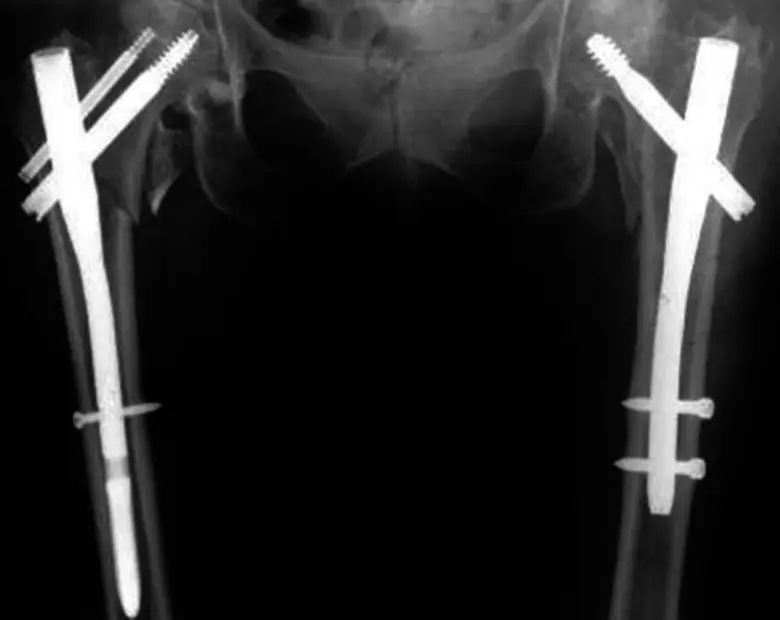

หากเกิดเรื่องที่เราไม่อยากให้เกิด นั่นคือ ผู้สูงอายุหกล้มกระดูกหัก โดยอวัยวะที่หักพบบ่อยใน ออร์โธปิดิกส์ ส่วน คือ ข้อมือ สะโพก และกระดูกสันหลัง จากการข้อมูลทั่วไปพบว่าหาก "ข้อมือหัก" หรือ "กระดูกสันหลังทรุด" กระดูกจะมีรูปร่างบิดเบี้ยวไป หลังก็ค่อมลงๆ แต่มักจะไม่ถึงขั้นเสียชีวิต ยกเว้นกรณีที่ทรุดไปมากหรือมีการกดทับเส้นประสาทก็ต้องรับการรักษาเฉพาะทาง แต่ถ้า "กระดูกสะโพกหัก" ปัญหาคือความเจ็บปวดทุกข์ทรมาน ไม่สามารถลุกยืนเดินได้ ต้องนอนติดเตียงเสี่ยงกับโรคแทรกซ้อนต่างๆ ถือเป็นเรื่องที่สำคัญ ซึ่งเกินกว่า ร้อยละ 95 ต้องได้รับการผ่าตัดเร่งด่วน แต่ที่สำคัญคือการรักษาแบบองค์รวมของหลากหลายสาขาอย่างมีระบบจะช่วยให้เกิดความรวดเร็ว ปลอดภัย ในส่วนวิธีการผ่าตัดในผู้ป่วยแต่ละคนนั้นแพทย์ต้องเลือกว่าเหมาะกับการรักษาวิธีใด เพราะมีรูปแบบการรักษาต่างๆ เช่น ผ่าตัดใส่แท่งโลหะยาวๆ มีสกรูยึด หรือมีเรื่องของการใช้ซีเมนต์เสริม บางรายอาจใช้ข้อสะโพกเทียม หลังจากผ่าตัดเสร็จแล้ววันที่ โรงพยาบาลกรุงเทพ-5 ผู้ป่วยต้องเริ่มทำกายภาพบำบัดเพื่อฟื้นฟูสภาพ พยายามให้ลุกออกจากเตียง ฝึกการนั่ง ยืน เดิน และการทรงตัว ซึ่งตรงนี้มีความสำคัญมาก เพราะผู้ป่วยกระดูกสะโพกหักส่วนใหญ่ที่นอนติดเตียง อาจส่งผลร้ายตามมา